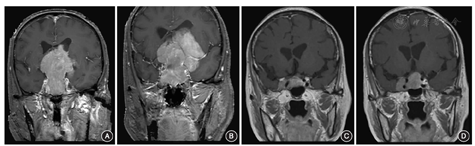

垂体腺瘤起源于垂体前叶,故所有肿瘤初始阶段均为鞍内肿瘤。肿瘤逐渐生长扩大时,受周围膜性结构的束缚而表现为不同的生长形式。当鞍膈反折形成靠前时,即患者鞍膈孔较大,且海绵窦内侧壁完整,肿瘤主要向鞍上生长,在通过鞍膈孔处形成"雪人征" ;当鞍膈反折靠后紧贴垂体柄时,即患者鞍膈孔较小,鞍膈张力较大,对肿瘤向上生长形成较大阻力,肿瘤主要向鞍内生长,表现为垂体窝扩大、鞍底骨质吸收,部分患者的肿瘤甚至突入蝶窦内生长,如此时海绵窦内侧壁同时发育不良,肿瘤可以在较小体积时就向两侧海绵窦扩展(图4)。